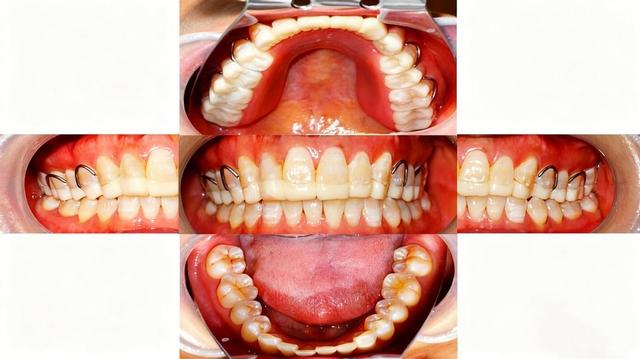

咬合问题:牙齿排列不齐(如龅牙、地包天)、缺牙后没及时修复(导致两侧咀嚼受力不均)、补牙/镶牙后咬合过高、牙周炎等口腔疾病引起的咬合异常等,都会让关节承受额外压力。

牙周炎会导致牙龈红肿、出血、牙槽骨吸收,牙齿慢慢松动、移位。牙齿位置变了,咬合关系就会“错乱”,颞下颌关节为了适应新的咬合,会被迫调整运动方式,时间长了就会出现疼痛、弹响。

缺牙后如长期不镶牙或种牙,导致邻牙倾斜、咬合错乱,颞下颌关节为了 “迁就”异常咬合,会长期处于偏移、紧张的运动状态,可能逐渐出现疼痛、弹响,压力会转移到另一侧。关节长期“一边忙、一边闲”,易出现劳损,进而引发TMD。